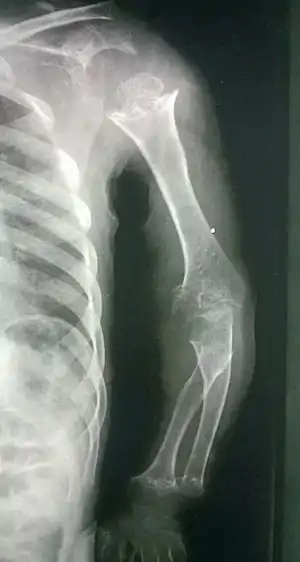

| Pseudoachondroplasia. Shoulders and Humeri. Note the dysplastic proximal humeral epiphyses, metaphyseal broadening, irregularity and metaphyseal line of ossification. These changes are collectively known as "rachitic-like changes". Lesions are bilateral and symmetrical. | |

- Together with rhizomelic limb shortening, the presence of epiphyseal-metaphyseal changes of the long bones is a distinctive radiologic feature of pseudoachondroplasia.

- Dysplastic/hypoplastic epiphyses especially of shoulders and around the knees.

- Metaphyseal broadening, irregularity and metaphyseal line of ossification. These abnormalities that are typically encountered in proximal humerus and around the knees are collectively known as “rachitic-like changes”.

- Radiographic lesions of the appendicular skeleton are typically bilateral and symmetric.